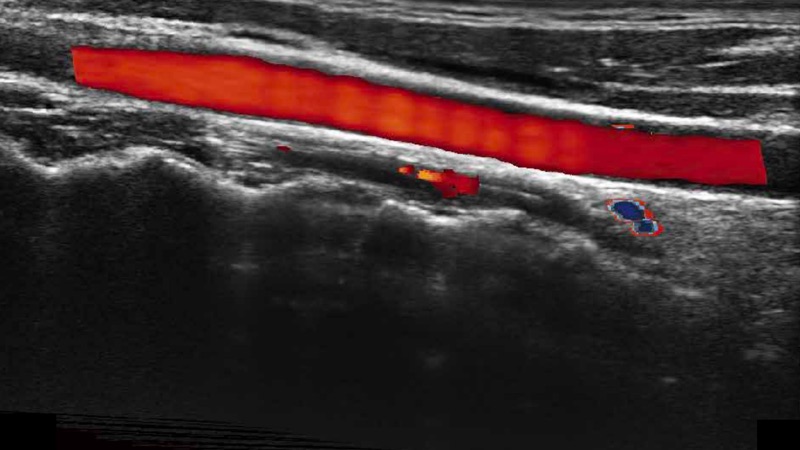

• 实时宽景成像技术

通过色彩血流和实时宽景相结合,可观察到完整的静脉或动脉的血流,方便医生检查。实时扫查过程中,如有任何操作失误也可以很容易地进行回扫擦除,而不会中断扫查。

临床图像